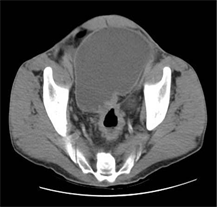

Abdominopelvic CT scan performed in 12 patients in our series confirmed the occlusive syndrome in all cases with small bowel dilatation of more than 25 cm upstream of the transition zone in 67% of our patients (Table 2). Colon dilatation of more than 50 mm upstream of the transition zone was found in 33% of our patients (Table 2). NHA in the digestive tract were an important argument for the diagnosis on CT and represented 83% of cases (Table 4, Figures 3-5). The sublesional syndrome, particularly the non-dilated digestive loops downstream of the transition zone, was found in 42% of our patients but the downstream digestive segment was dilated in 58% of cases (Table 3, Figure 5). The transition zone was identified in the 12 patients and the site was slender in 48 patients or 55.2% and colic in 39 patients or 44.8% (Table 3). The etiologies were dominated by flanges in 46 patients and tumors in 9 patients (Table 5, Figure 5).

Figure 3. Abdominal CT axial section without PDC injection showing distended digestive loops presenting a saw-toothed mucosal fold (arrow) indicating their slender nature.

Figure 4. Abdominal CT axial cut with PDC injection showing distended loops with haustrations (arrow) indicating their colic nature.

Figure 5. Abdominal CT axial section without PDC injection showing a transition zone made of stenotic thickening of the rectosigmoid hinge.